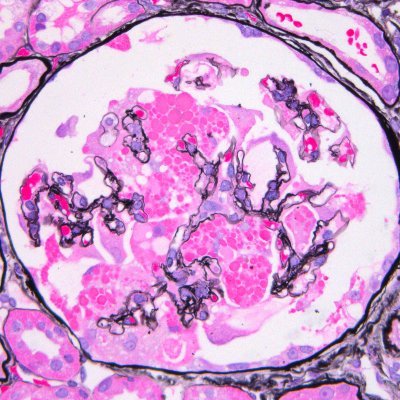

A simple classic case, because if you need to know something for path and nephrology boards in renal path, you need to know about PLA2R positive membranous. It was a game changer. For patient care too. It all started here nejm.org/doi/full/10.10…

MessiasNidia's tweet image. A simple classic case, because if you need to know something for path and nephrology boards in renal path, you need to know about PLA2R positive membranous. It was a game changer. For patient care too.  It all started here nejm.org/doi/full/10.10…